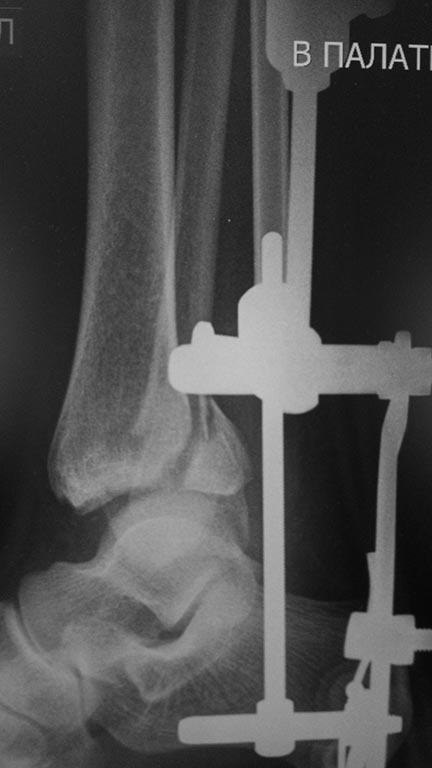

Мужчина, 1987 г.р. получил травму 10.2014. ДТП. Закрытый двухлодыжечный перелом костей костей левой голени, перелом заднего края большеберцовой кости с подвывихом стопы кзади, кнаружи.

Наложен дистрактор. Операция 10.2014: закрытая репозиция, остеосинтез спицами, винтами. В дальнейшем произошло ожидаемое усугубление нарушений взаимоотношений в голеностопном суставе.

На момент обращения: жалобы на боль в левом голеностопном суставе.Работать не может (работает водителем). Без дополнительной опоры может пройти до 20-30 метров. Отечности мягких тканей нет.

Какой план лечения,на Ваш взгляд, предпочтительнее в данном случае? Возможно ли одномоментно устранить подвывих или только на аппарате Иллизарова? Первичные снимки после травмы отсутствуют. Критично ли "растоптана" латеральная суставная поверхность большеберцовой кости?

Мне кажется, что вопрос, поставленный Вами: "Возможно ли одномоментно устранить подвывих или только на аппарате Иллизарова?", отражает не совсем ясное понимание ситуации. Что значит устранить подвывих? А пластику ложных суставов внутренней лодыжки и заднего края большеберцовой кости не нужно делать? И ось голеностопного сустава нужно исправлять. То есть делать остеотомию наружной лодыжки (если она срослась, по снимку не очень понял). Артродез голеностопного сустава в такой ситуации очень сложен. Если же добиться сращения всех переломов в правильном положении, артродез вполне можно отсрочить на несколько лет, что для молодого пациента достаточно важно. Но в конечном счете все определяется Вашим умением и ясным представлением того, чего Вы хотите добиться своей операцией. Во вложении - в чем-то похожий случай. Оперировал эту пациентку 23 лет 11 лет назад через 8 месяцев после похожего на представленный Вами остеосинтез. На первой операции перелом малоберцовой кости в нижней трети был просто не замечен. За счет восстановления оси быстро развившийся артроз протекал благоприятно. В результате артродез был выполнен только в прошлом году, через 10 лет после второй операции. И боли беспокоили пациентку только в течение года перед артродезом.